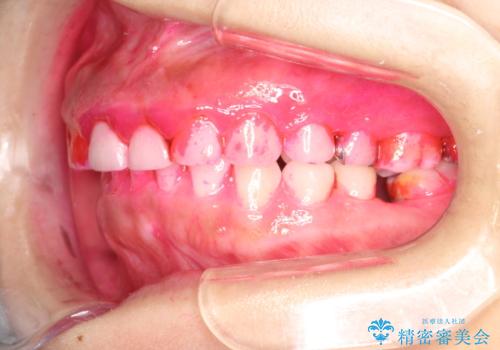

開始前

かなり久しぶりの歯科医院との事で、全体的に古くからの歯垢・歯石が多く付着していたため、自費クリーニング(PMTC)60分コース・歯周ポケット検査(保険適応)を行いました。